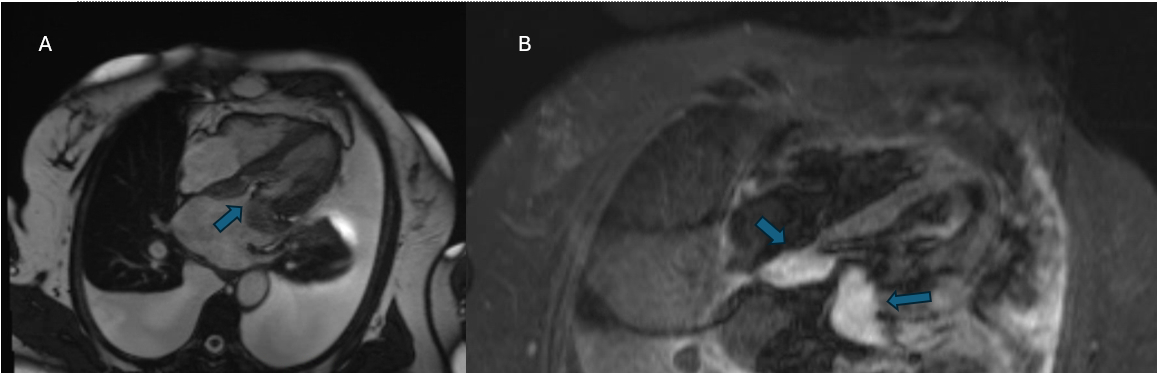

A 67-year-old woman presented to the pulmonary clinic for a work-up of a left-sided pleural effusion with a 2-month history of exertional dyspnea, palpitations, and dry cough. The Holter monitor identified episodes of atrial fibrillation, and ECHO showed moderate to severe mitral stenosis and preserved ejection fraction of 59%. Thoracocentesis revealed lymphocytic effusion, negative cytology, and culture; other labs showed unremarkable immunological markers. A PET scan revealed a small left pleural effusion with minimal FDG uptake and nonspecific increased FDG uptake within the left atrial appendage. TEE revealed a large left atrial mass, which was initially thought to be a left atrial thrombus or myxoma. Cardiac MRI characterized the mass as hyperintense on T2-weighted sequences, enhancement on the first pass of gadolinium, and hyperintense on late gadolinium enhancement sequences, suggesting malignancy, as opposed to a thrombus. The patient had tumor excision, revealing a 7.5 cm Intimal-type sarcoma with non-eventful post-op recovery.